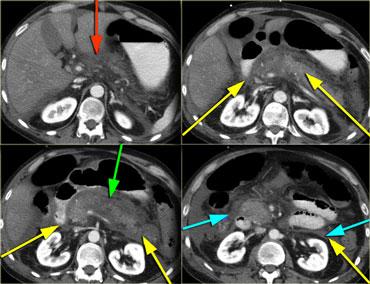

- Có thể được sử dụng như một hướng dẫn cho phương pháp phẫu thuật

Các ổ dịch quanh tụy có thể được tiếp cận qua đường xuyên gan (mũi tên đỏ), xuyên dạ dày (mũi tên xanh lá) hoặc xuyên thành bụng (mũi tên xanh dương), tuy nhiên đường tiếp cận được ưu tiên là duy trì trong khoang sau phúc mạc (mũi tên vàng).

Đường tiếp cận sau phúc mạc có một số ưu điểm:

- Cùng khoang với tụy.

- Không bị nhiễm khuẩn từ hệ vi khuẩn đường ruột.

- Lợi dụng trọng lực.

- Ống dẫn lưu chạy song song với nền tụy.

- Đường tiếp cận có thể được sử dụng để hướng dẫn phẫu thuật xâm lấn tối thiểu.